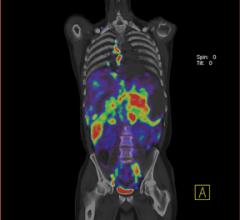

TechnologyAs Discovery PET/CT 600 series continues to expand, GE Healthcare introduced the Discovery PET/CT 690 – a molecular imaging tool designed go beyond the needs of the clinical practice and provide the necessary tools and technologies to explore the future of PET/CT imaging.